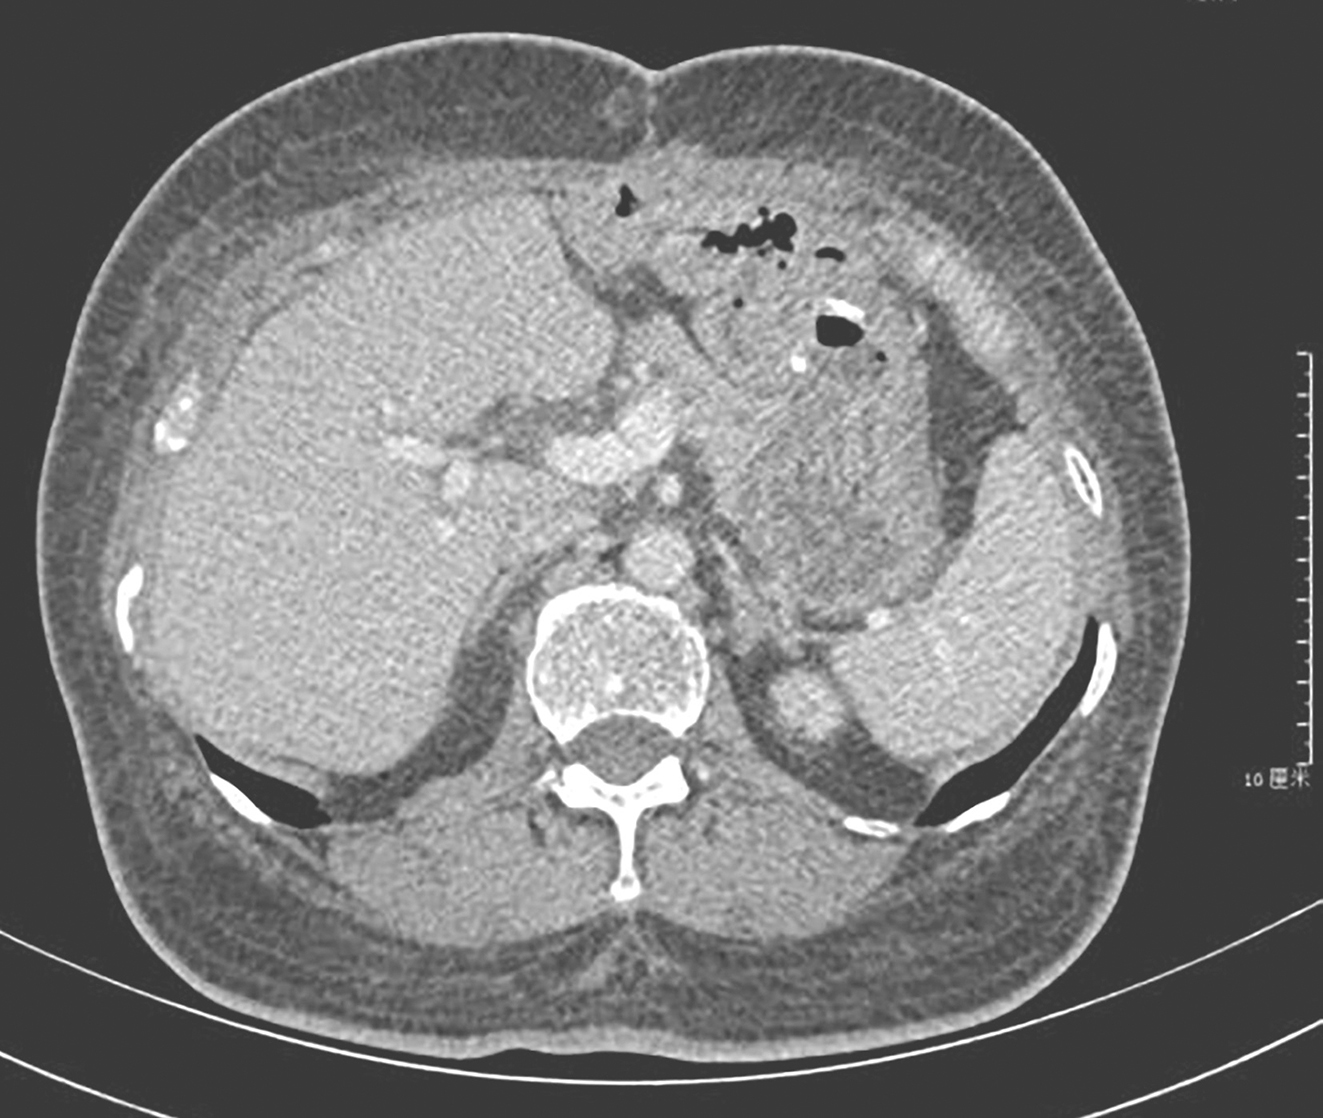

患者于术后第13天恢复出院。术后第14天给予伊马替尼靶向治疗,400mg/d。截至2019年6月,随访45个月,患者服药期间出现水肿、白细胞减低(2度)等不良反应,未行特殊治疗,症状缓解,复查全腹部增强CT未发现明显肿瘤复发转移迹象(图5)。

图5术后45个月复查CT